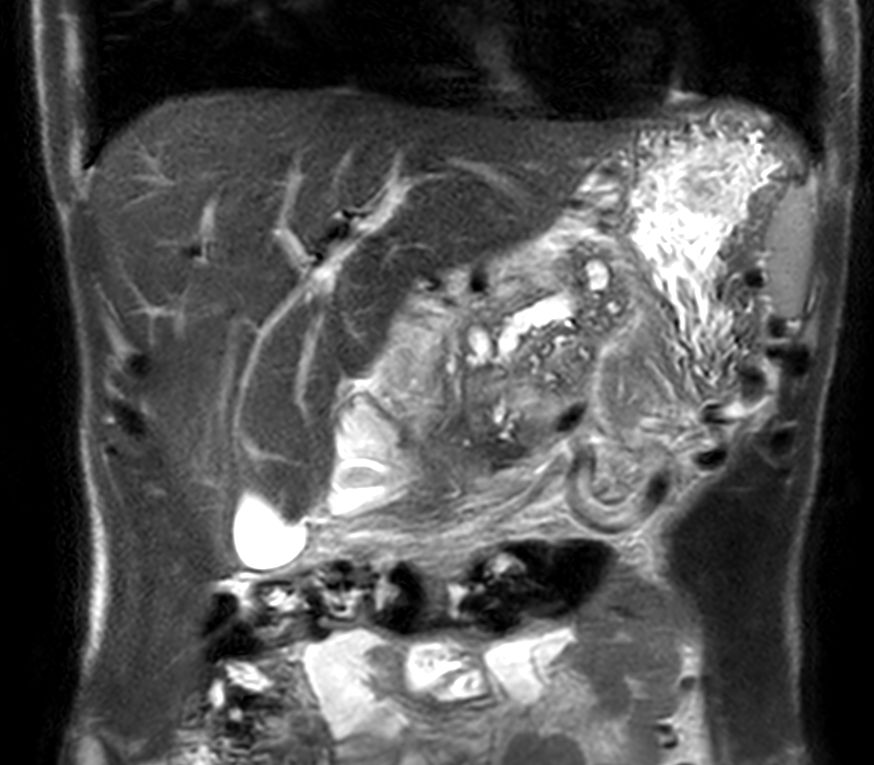

Coronal T2w TSE single shot